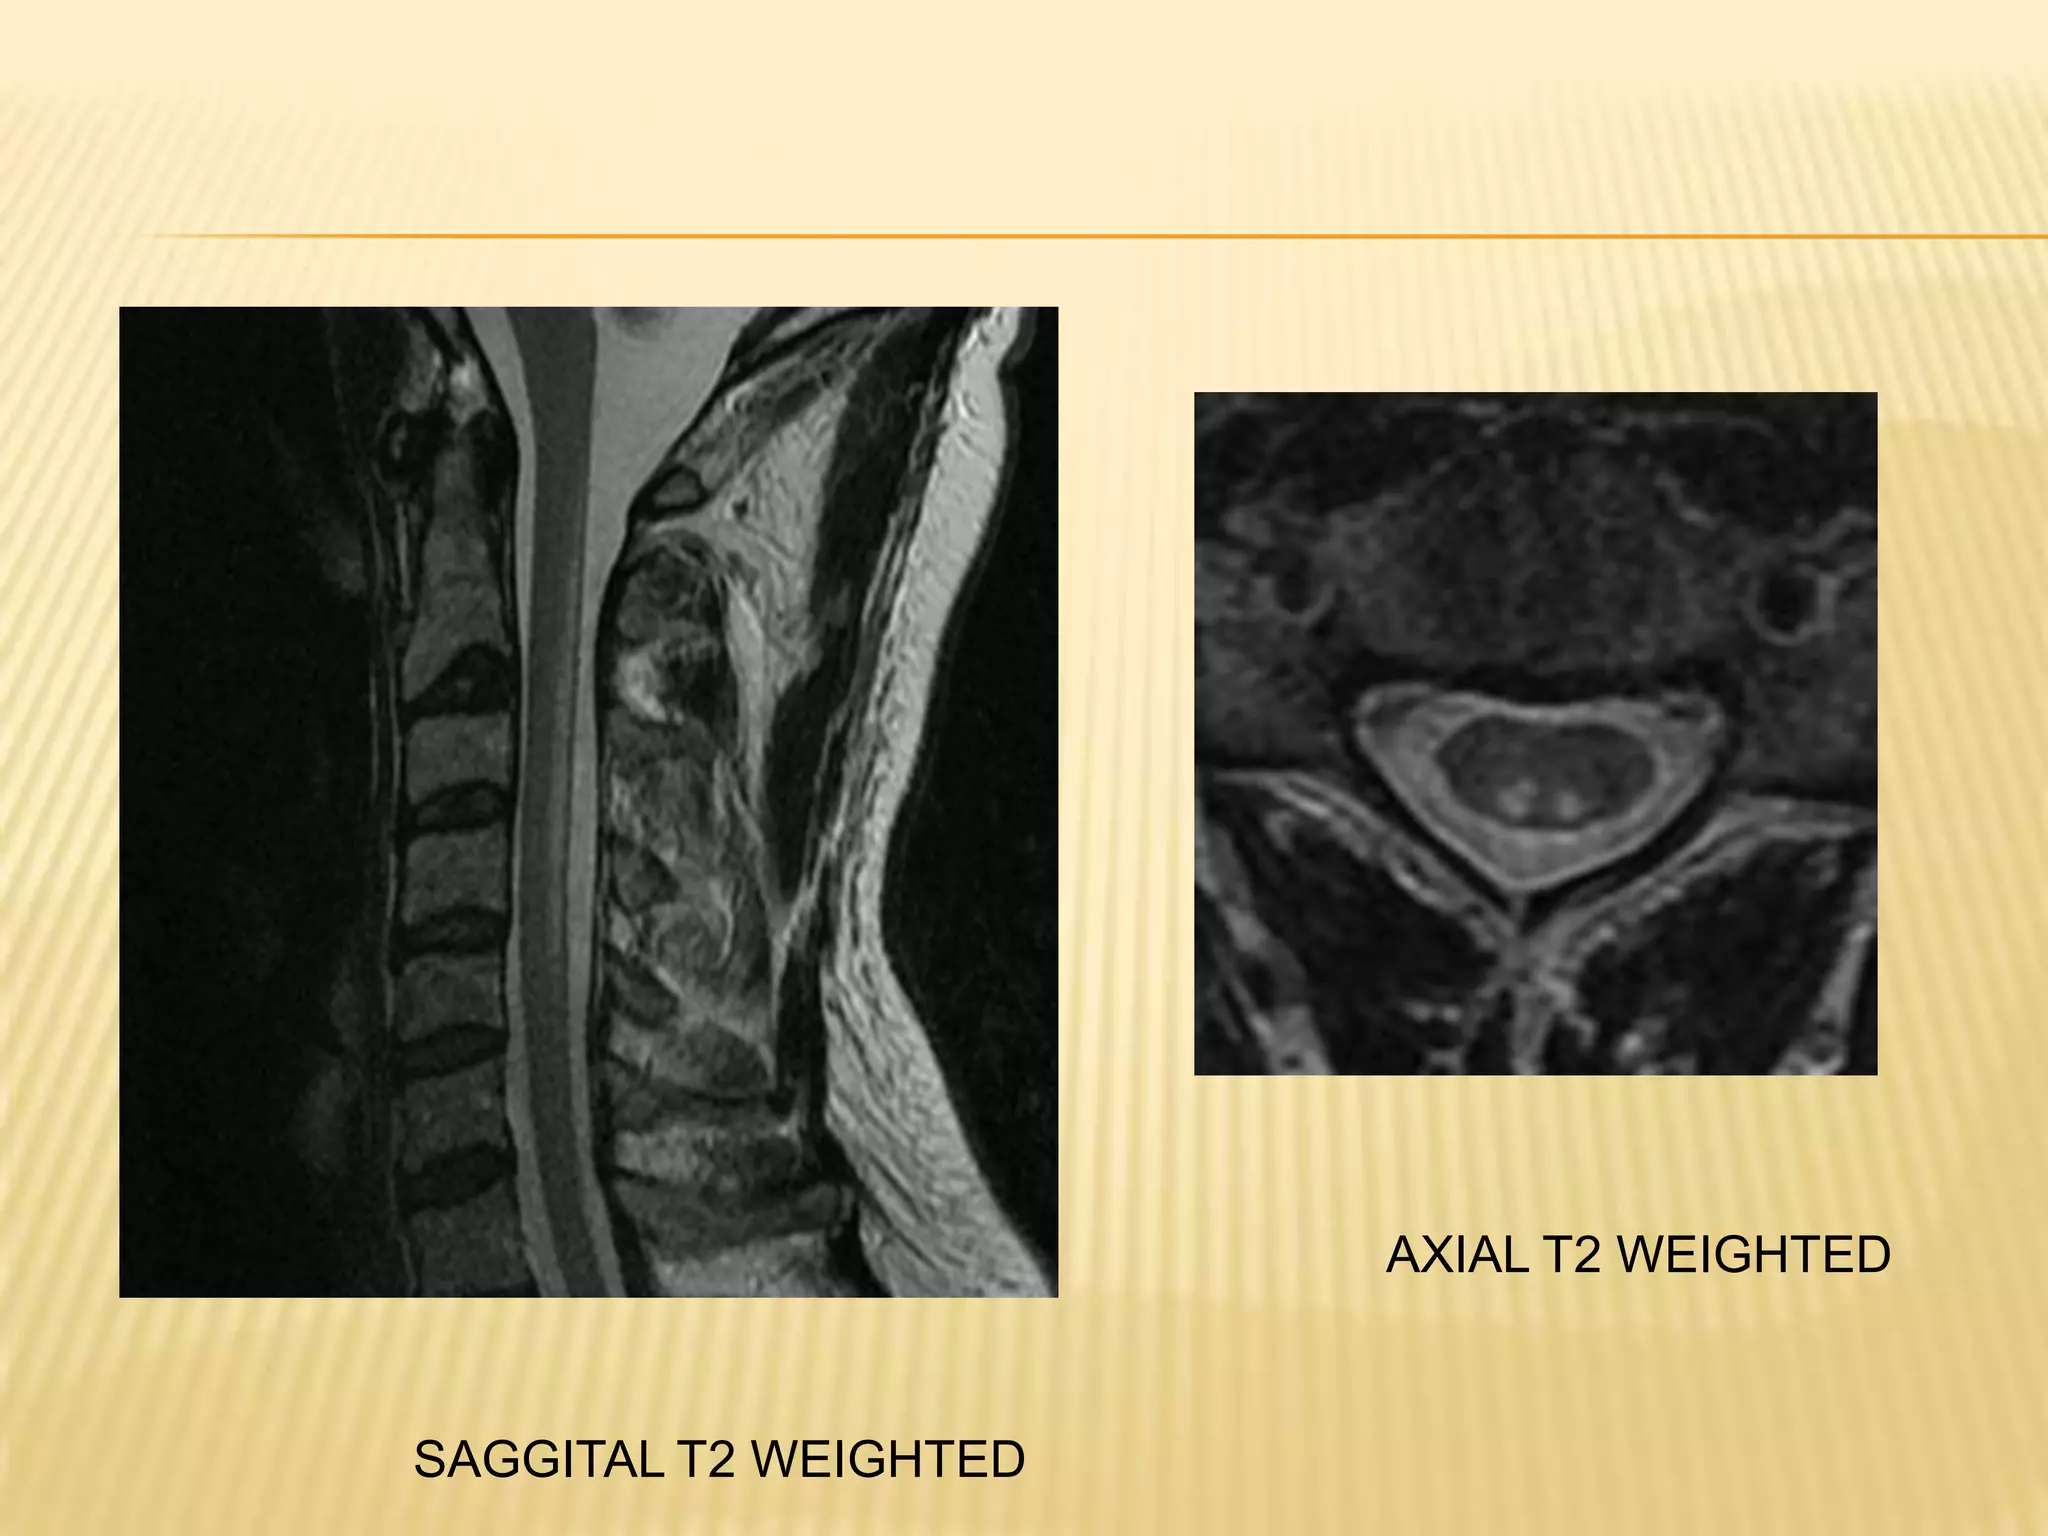

 MRI SPINE –hyperintense T2 WEIGHTED

signal in posterior and lateral colums

AXIAL T2 WEIGHTED

SAGGITAL T2 WEIGHTED

Tests for causeof deficiency-serum gastrin, anti intrinsic factor antibody (elevated gastrin in 30% elderly )  MRI SPINE –hyperintense T2 WEIGHTED signal in posterior and lateral colums 